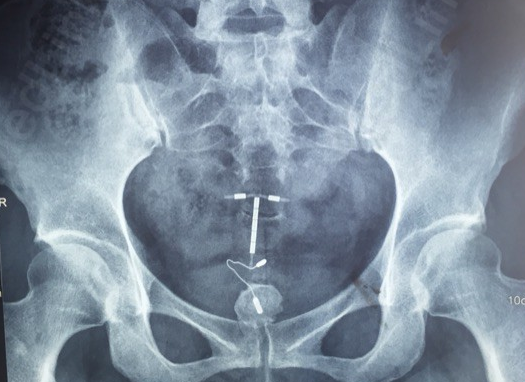

图片

多发性膀胱结石和单发膀胱结石

异物(节育环)导致的结石